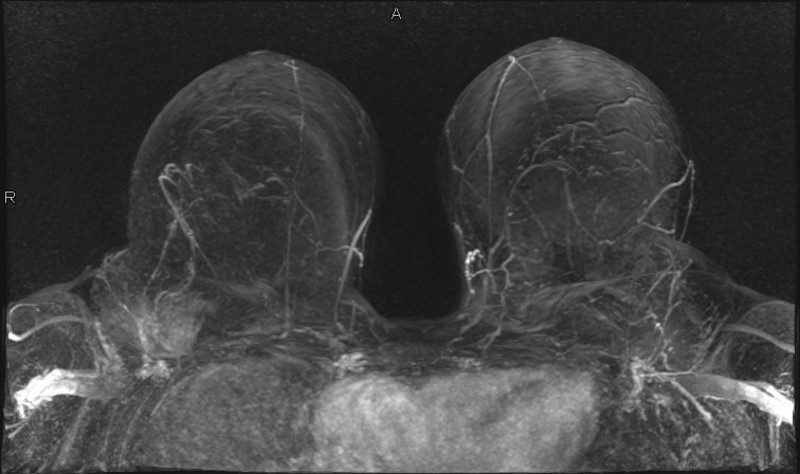

Die MR-Mammographie, eine kernspintomografische Untersuchung der Brustdrüse, ist ebenfalls eine hochempfindliche Technik und ergänzt üblicherweise die Mammographie- und Ultraschalluntersuchung.

Sie kommt typischerweise dann zum Einsatz, wenn ein besonders erhöhtes Brustkrebs-Risiko vorliegt, zum Beispiel bei einem gehäuften Auftreten von familiärem Brust- und/oder Eierstockkrebs oder eigenen Risikofaktoren.

Bei der MR-Mammographie wird die Brust in einem starken Magnetfeld untersucht. Ein nicht Jod-haltiges, sehr gut verträgliches Kontrastmittel wird während der Untersuchung in eine Armvene gespritzt. Das Kontrastmittel dient dazu, eventuell vorhandene Tumore durch ihre höhere Durchblutung und die damit verbundene stärkere Kontrastmittelaufnahme gegenüber dem normalen Brustdrüsengewebe besser abzugrenzen. Durch den hohen Gewebekontrast, die Darstellung und die Messung der Gewebedurchblutung durch das Kontrastmittel, ist es in vielen Fällen möglich, Veränderungen überhaupt erst zu erkennen oder noch genauer zu charakterisieren.